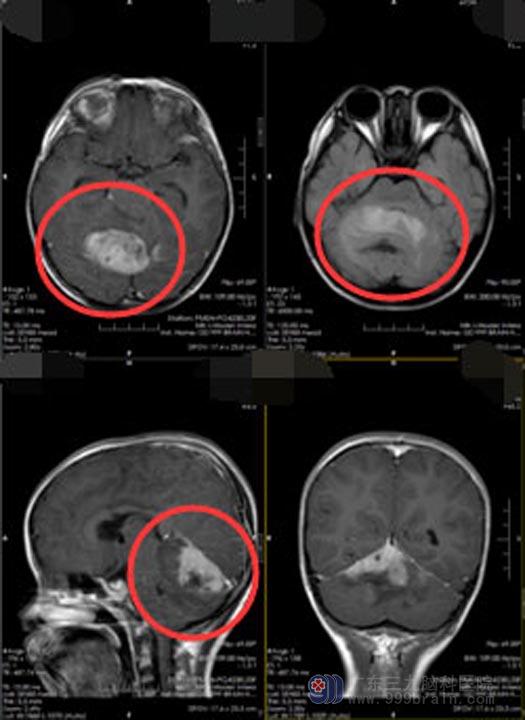

听从了同村热心人的建议,小妍爸妈带着她来到了广东三九脑科医院神经外五科。入院后头颅MR检查显示:小脑蚓右侧占位性病变,累及双侧小脑半球、小脑幕,结合DWI,考虑小脑恶性肿瘤,髓母细胞瘤可能。

医院副院长、神经外五科主任鲁明带领团队制定了缜密的手术方案后,于11月25日在全麻下行“双侧小脑半球巨大肿瘤切除术+硬脑膜修补术+后颅窝去骨瓣减压术”,肿瘤血供丰富,双侧小脑半球水肿明显;沿小脑幕下切除部分小脑后,见肿瘤呈灰红色质地较软,边界清,肿瘤存在卒中,肿瘤主体位于幕下右侧小脑半球累及对侧,肿瘤沿小脑幕生长至深部达小脑幕与大脑镰结合部,沿边界边止血边全切除肿瘤。